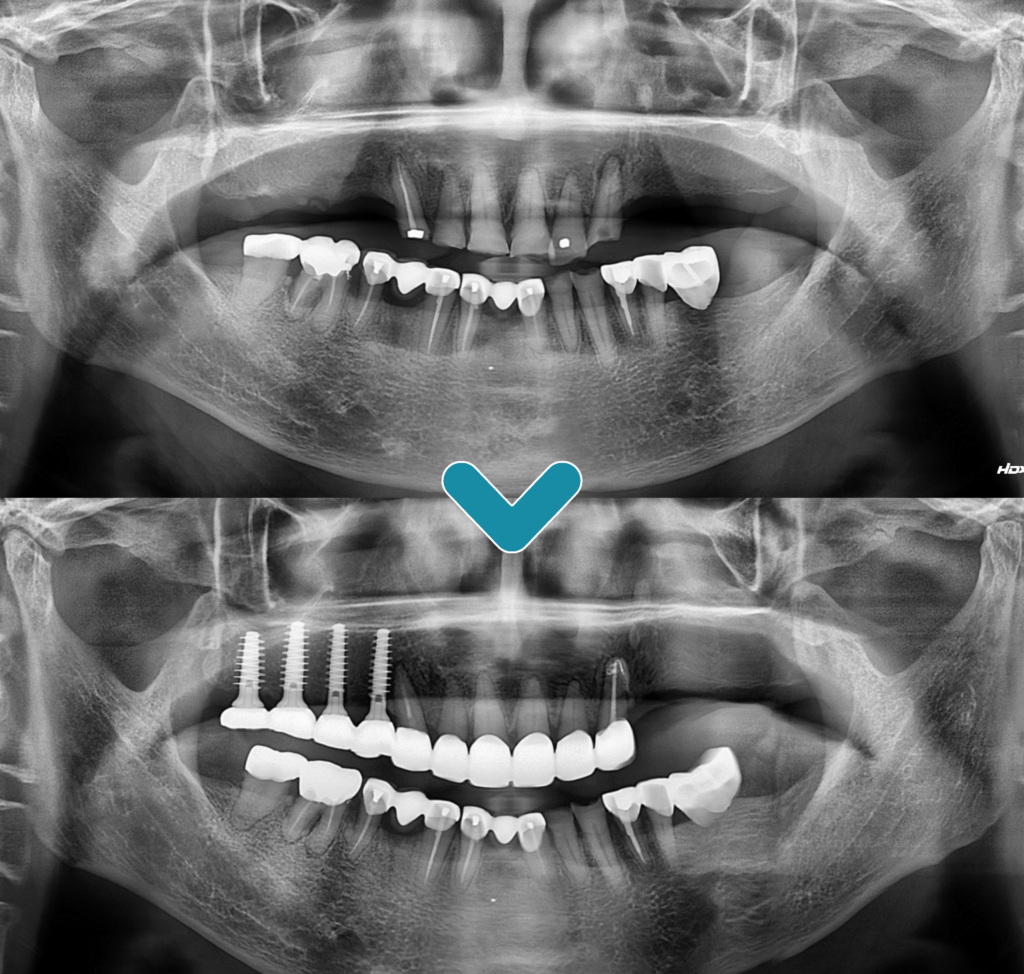

임플란트를 식립 할 때 위아래의

교합을 정교하게 맞추기 위해 아래쪽

보철물을 새로 제작하였으며,

닳아있던 앞니 보철치료까지 완료하여

2년 후 정기 검진을 오셨을 때

촬영한 파노라마 사진입니다.

매직 코어 임플란트의 식립을

통해 빠른 회복과 더불어 환.자분의

꾸준한 관리로 건강하게 유지가

잘 되고 있음을 알 수 있었습니다.